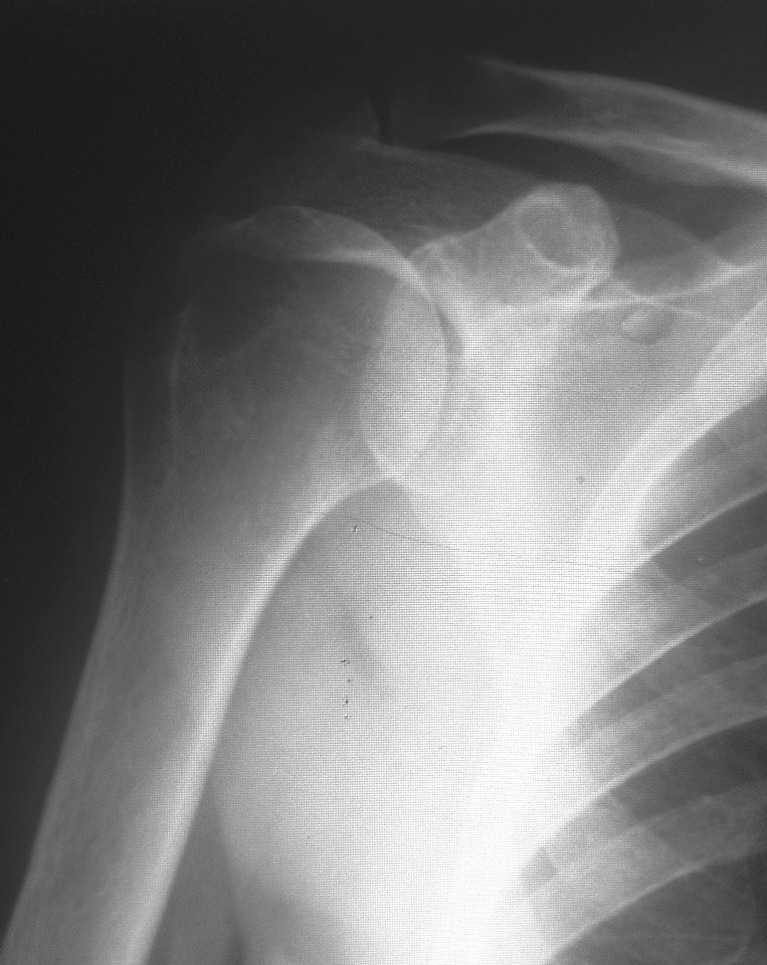

Уважаемые коллеги! Поздравляю всех с наступившим Новым Годом, наступающим праздником Светлого Рождества Спасителя, и прошу помощи в виде ваших комментариев по представленному мною рентгеновского снимка правого плеча. Женщина, 1959 г.р.. Жалоб на функцию правого плечевого сустава не предъявляет, движения в полном объеме, активные и пассивные без ограничений и боли. Меня смущает на данном снимки состояние головки.Сам снимок был проведен с целью контроля состояния сустава, так как больная в 2003 году проходила у меня лечение по поводу правостороннего осифицирующего тендинита надостной мышцы. Если потребуются снимки 2003г. скажите и я размещу.

Меня смущает на представленном снимке <просветление> в области бугра и головки плеча. Или это только мои необоснованные сомнения?

А что вас смущает7 Остеопороз бугорка? Так это следствие хронического инсерционита вращателной манжеты. Сделайте снимок в более мягком, чем здесь режиме.

Да, это и смущает, нет ли там признаков формирования полости? Дополнительные снимки больная не хочет делать.

"Меня смущает на представленном снимке "просветление" в области бугра и головки плеча. Или это только мои необоснованные сомнения?"

На первый взгляд непохоже на агрессивный процесс. Возможно, из-за качества снимков, но мне кажется, что на лопатке и на ключице имеются какие то аномальные пятна?

Отсутствие процесса в других участках тела и отсутствие жалоб, наличие характерной локализации, говорит о том, что процесс напоминает ?псевдокисту" головки плеча.

Кроме головки плеча "псевдокиста" встречается еще в передних отделах пяточной кости.

На фоне клинического благополучия, процесс обычно диагностируется в случайных рентген исследованиях.

Из-за отсутствия типичного воспалительного процесса в костномозговой части в Магнето Резонансовых Исследованиях "псевдокиста" показывает нормальный сигнал, поэтому первоочередно необходимо сделать качественные ренген снимки, которые увеличат шансы заметить случайные ?аномальные" находки и установить правильный диагноз.

Конечно, снимки с отведением не помешали бы, но кроме остеопороза у больной других патологических изменений нет